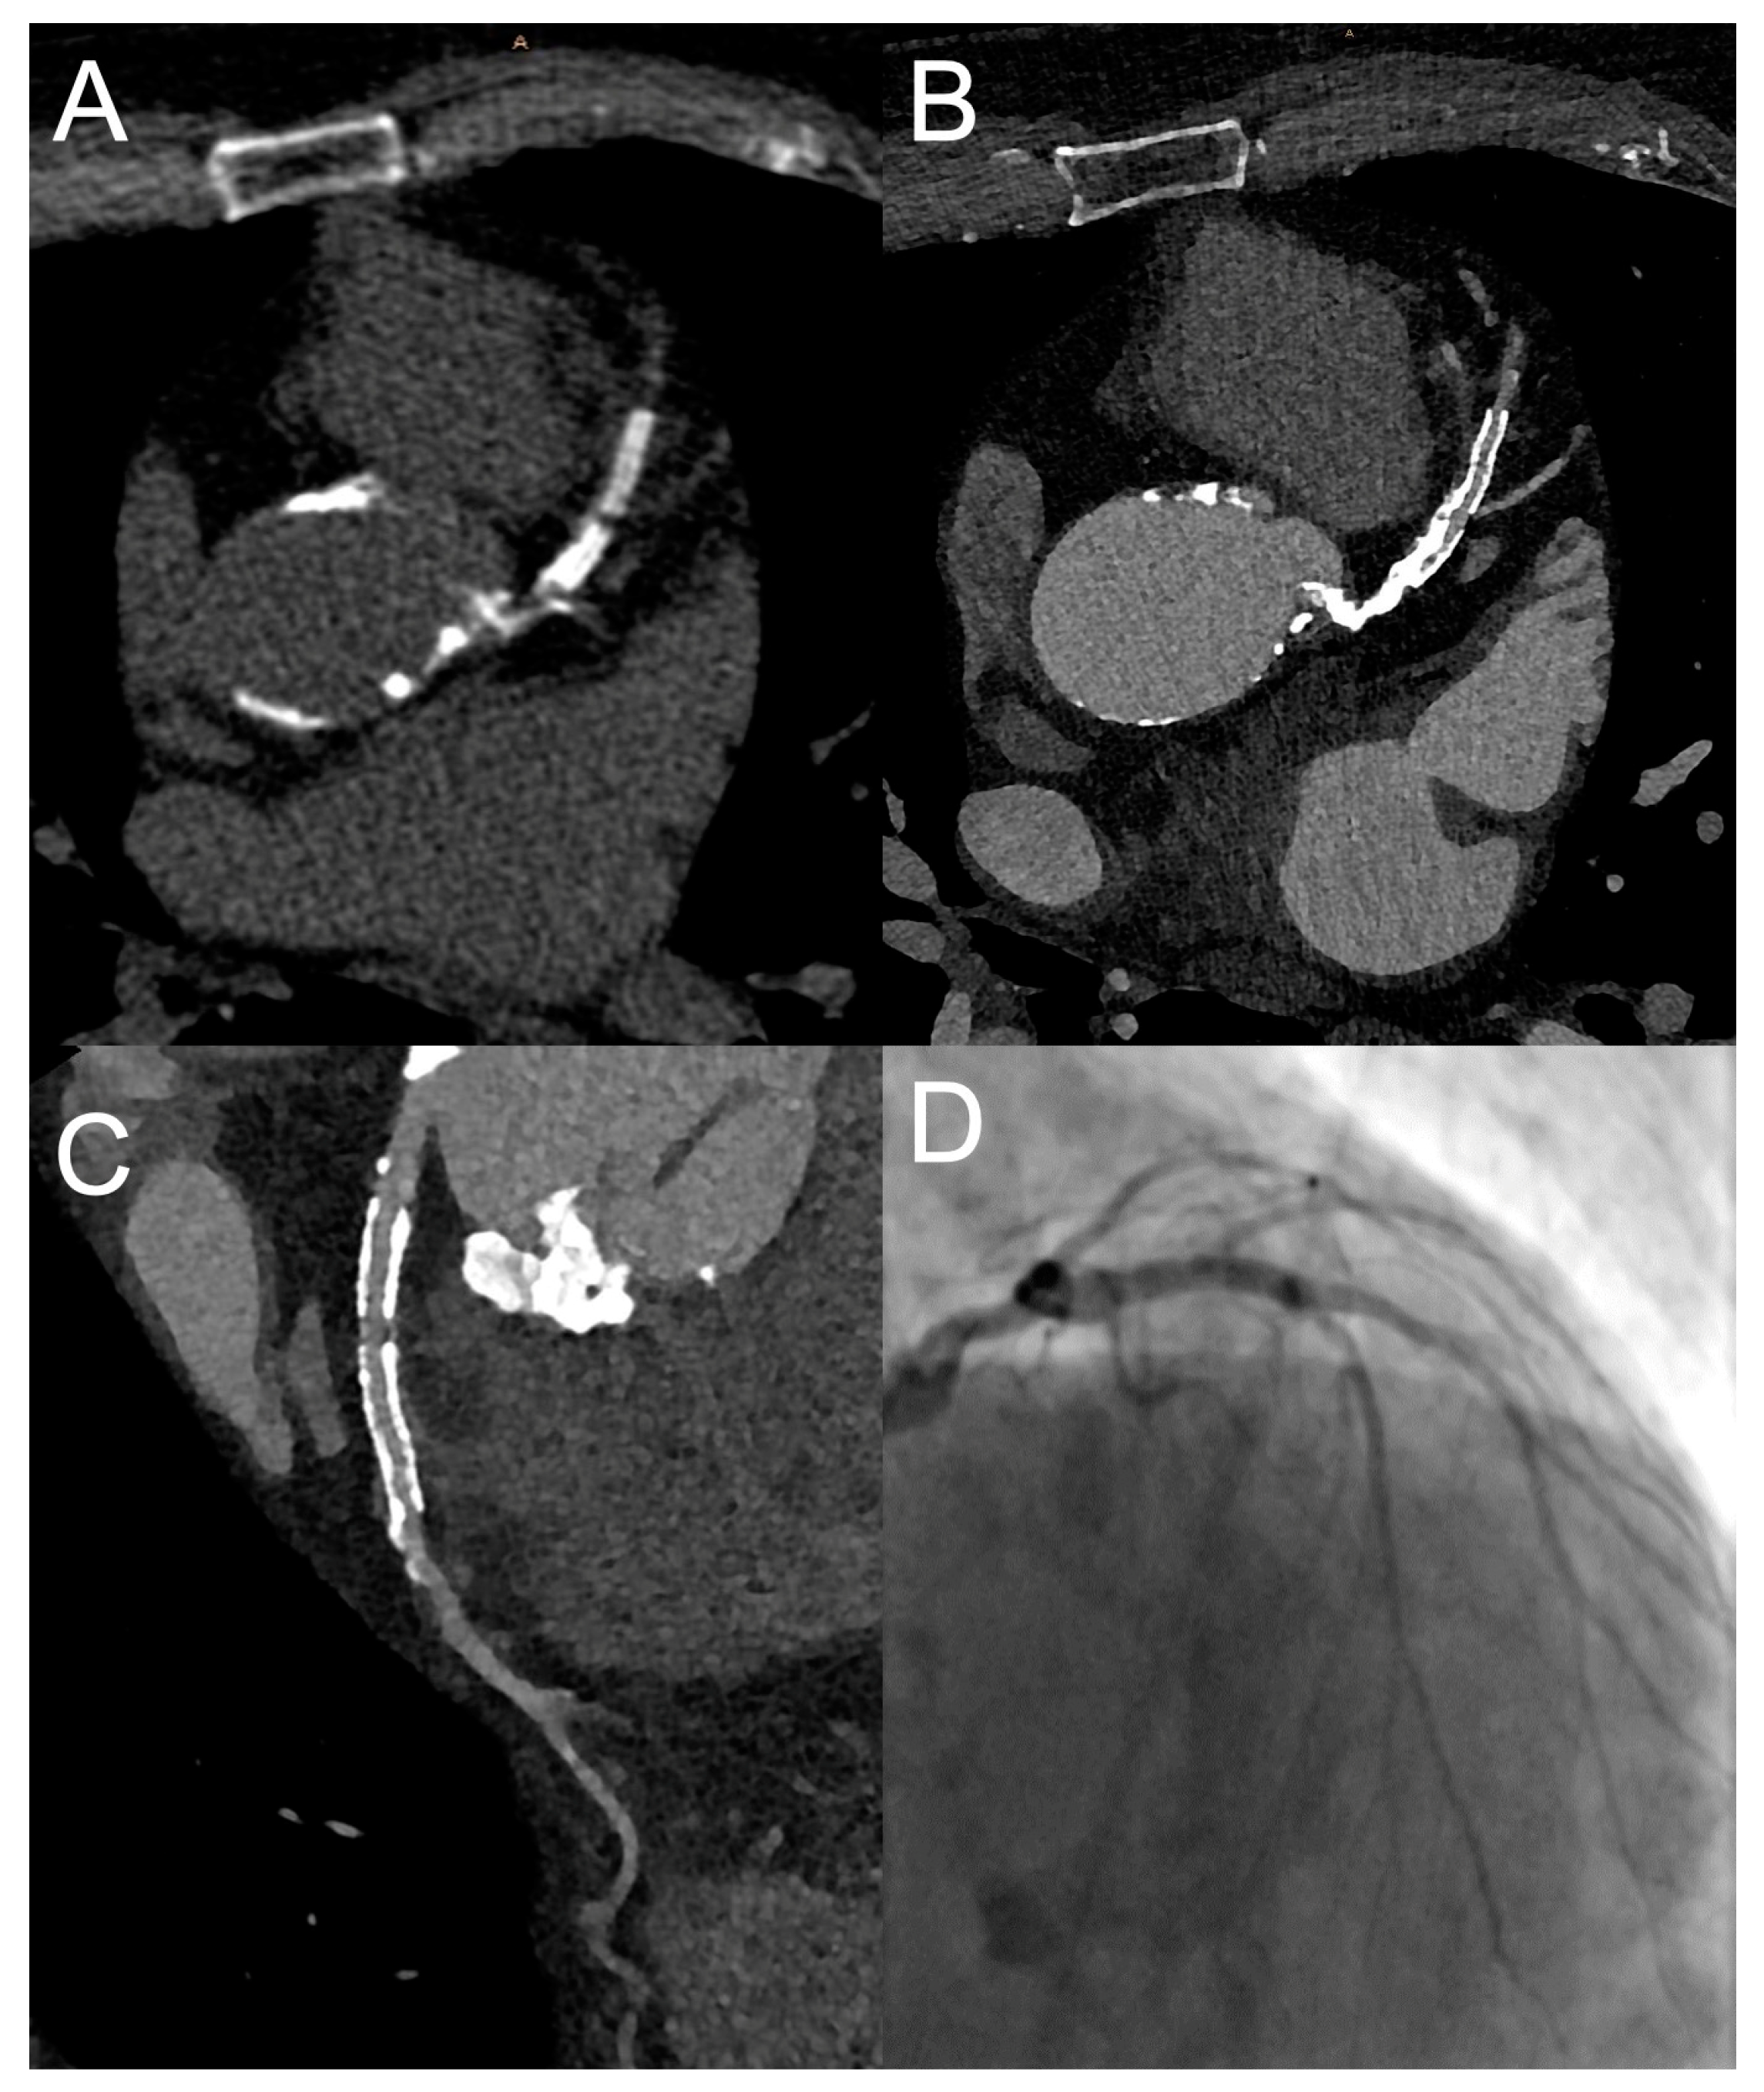

Figure 1. Imaging example of a stress CMR. A 58-year-old female patient with atypical angina symptoms and low pretest probability was referred for a stress CMR. The stress perfusion imaging revealed an extensive perfusion deficit (red arrows) of the anterior and anteroseptal wall on the basal (A), mid-ventricular (B) and apical (C) slice. An invasive coronary angiography showed a subtotal stenosis of the proximal left anterior descending artery (LAD) and the diagonal branch.